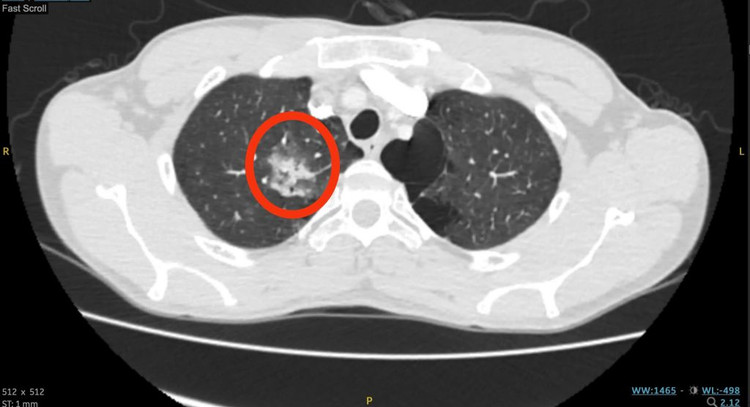

Tại Khoa Cấp Cứu, anh N. được các bác sĩ chỉ định chụp CT lồng ngực ghi nhận có tổn thương vùng đỉnh phổi hai bên, có hình ảnh xuất huyết nhu mô kèm tăng sinh động mạch phế quản thùy trên phổi phải.

| Hình ảnh CT vùng tổn thương trước can thiệp - Ảnh BVCC |

Theo BS.CKI. Phạm Khắc Tường – Trưởng Khoa Nội Hô Hấp BVĐK Xuyên Á cho biết: “Trường hợp của bệnh nhân N. là tình trạng ho ra máu lượng nhiều, chưa có tiền căn bệnh phổi nhưng người bệnh hút thuốc lá khá nhiều khiến khí phế thủng rải rác ở thùy vùng trên phổi hai bên, tổn thương phổi bên phải.”

Trước tình huống này, các bác sĩ khoa Nội Hô hấp, Nội Tổng Quát và Can Thiệp Mạch đã tiến hành hội chẩn, xác định đây là tình trạng ho ra máu nặng kèm tăng sinh động mạch phế quản bên phải.